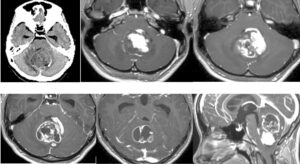

手術は通常通り行われ、顔面神経の麻痺を起こさずに摘出は終了し、うまくいったと考えていました。しかし術後より覚醒障害が続き、強い小脳腫脹を生じたため、術後脳室ドレナージ術、バルビタール麻酔療法、気管切開まで行い急性期を乗り切りました。術前より下肢静脈血栓症を合併していたことと、Petrosal veinが通常より広範囲の静脈環流を行っていたためと考えられます。現在、覚醒し、四肢が動くようになってきました。

手術は通常通り行われ、顔面神経の麻痺を起こさずに摘出は終了し、うまくいったと考えていました。しかし術後より覚醒障害が続き、強い小脳腫脹を生じたため、術後脳室ドレナージ術、バルビタール麻酔療法、気管切開まで行い急性期を乗り切りました。術前より下肢静脈血栓症を合併していたことと、Petrosal veinが通常より広範囲の静脈環流を行っていたためと考えられます。現在、覚醒し、四肢が動くようになってきました。